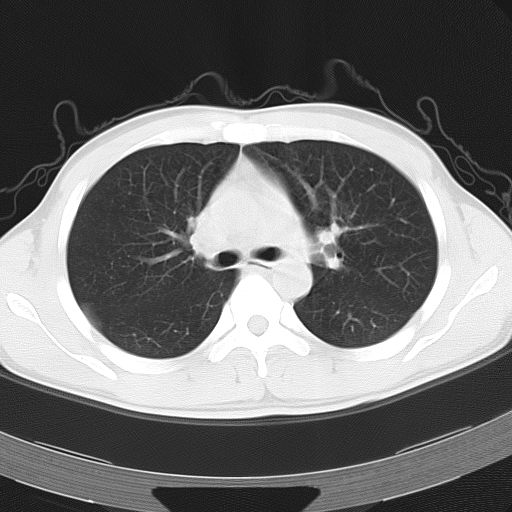

男,34岁,咳嗽2~3个月,无咳血,病初有发热。

两上肺磨玻璃样改变,均位于肺外周,考虑1、肺泡蛋白沉着症?2、肺泡炎?请询问有无养鸟史 3、脱屑性间质性肺炎?建议进一步检查、复查随访

两上肺的ggo,靠近胸膜,不是以节段分布,青年男性,个人意见为吸入性的真菌感染可能为大------------呼吸内科医生

两肺上叶近胸膜磨玻璃样阴影,考虑1、炎性病变。 。2、过敏性炎症?

病灶特点:

分布在肺野的外带,病灶边缘清楚,病灶以磨玻璃影为主夹杂少许纤维状高密度影

支持zhangzhongshou主任,考虑蛋白沉着症可能性大

病变分布以双上肺叶外带明显,双下肺未见异常,此一点不十分支持肺泡蛋白质沉着症,病变未见铺碎路石征,也不肺泡蛋白质沉着症。考虑间质性肺炎,结核不除外。

肺泡蛋白沉积症;胸膜下区磨玻璃样,实变区见纹理走形,地图样改变。做mri。

再仔细阅读该病人的ct片,我们不难发现,病例所表现的正是外围型的肺泡蛋白沉积症表现,即:为多发性条片状、斑片状及斑块状高密度影,弥散、对称或不对称分布于两肺或一侧肺外围部位。病变区与正常肺组织及脏层胸膜面分界清晰,呈地图样改变。

所以,我本人的意见也是趋向于肺泡蛋白沉积症的诊断,尽管最后诊断还是要根据支气管肺泡灌洗物检查或经纤支镜或剖胸活检作出病理诊断。或痰液检验:咳出的痰经80%乙醇固定,pas染色有15%阳性的脂质。

该病人经过1周抗炎治疗,病灶基本消退,仅存毛玻璃样改变。